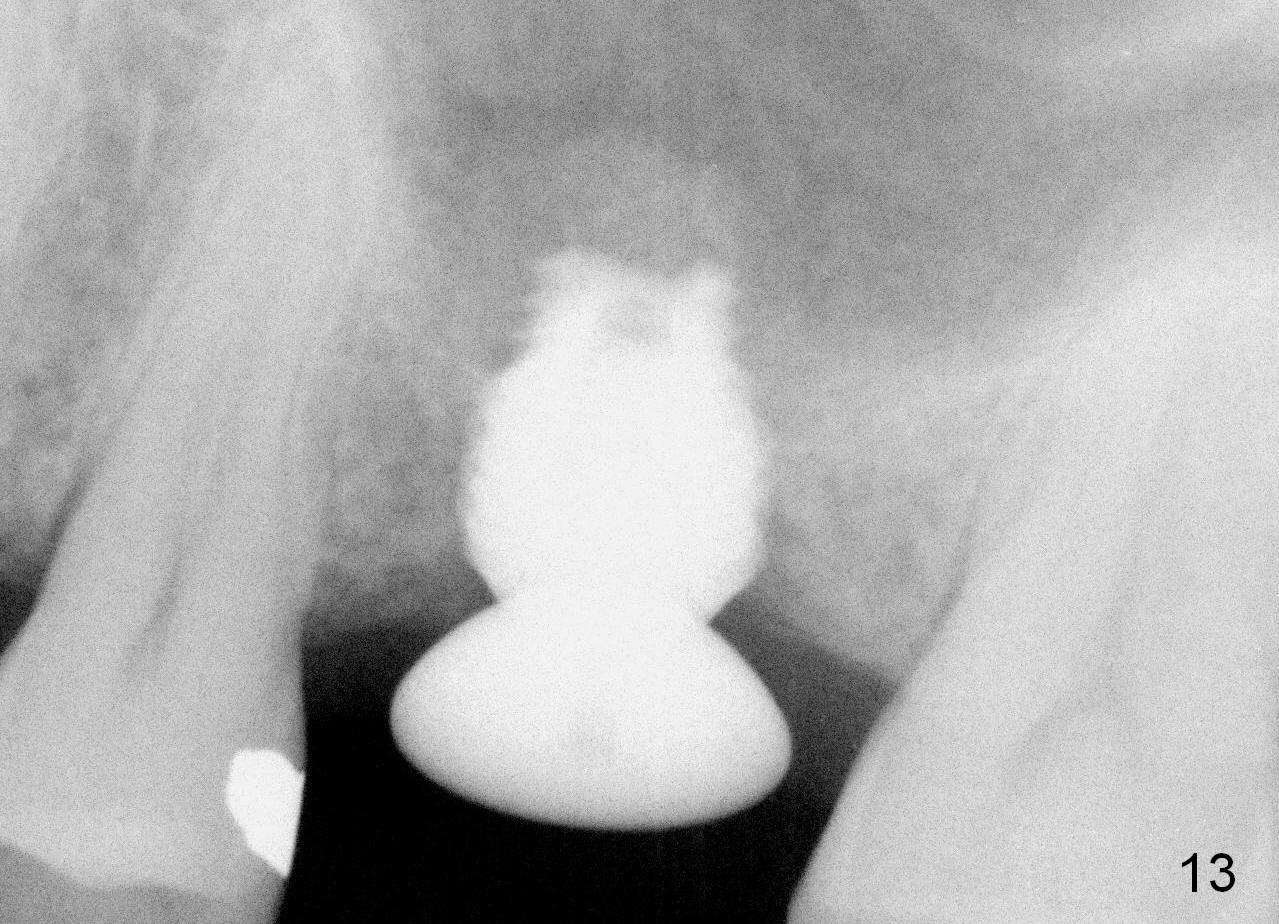

A 45-year-old man has lost the tooth #14 for a while (Fig.1); bone height is 5.4 mm. An extra wide and short implant is planned. Torus palatinus is large, suggesting that bone density should be high. A 6 mm tissue punch is chosen, but it is placed more palatal. If it were placed in the middle of the ridge, there would be no buccal keratinized gingiva (incision may avoid this issue). Additionally, the buccal portion of punch is made incomplete so that there is pedicle on the buccal side when the flap is raised (Fig.4,8: F). It is expected that the excess portion of keratinized tissue will form thick gingiva buccally. Osteotomy proves that bone is dense (Fig.2 (4.5x11 mm tap). Typical sinus lift is finished with placement of 6.4x6 mm (extra wide) bone-level implant (Fig.3, >55 Ncm). Following further torque, Fig.4 shows that the implant (I) is sub-gingival (<). Bitewings are taken to confirm that the implant plateau is at the crestal level (Fig.5,6 ^). PA shows sinus lift (Fig.7 *). The lingual aspect of the implant and healing abutment (H) is further bone grafted and covered by collagen dressing (Fig.8 *). The wound is protected with perio dressing. When the latter dislodges 7 days postop, the collagen dressing and bone graft are lost as well (Fig.10), while the buccal flap remains vital (Fig.9). The lingual exposed plateau should be able to heal normal. The collagen dressing should have been fixed in place by suture or as simple as a dental floss. There is mild nasal hemorrhage 1-2 days postop, possibly related to sinus membrane perforation and inability of Collagen Dressing to cover the perforation and contain the bone graft. When the patient returns for #9 implant placement in 3 weeks postop, the buccal flap reduces in size (Fig.11 *), while the palatal wound has healed with minimal exposure of the implant (Fig.12). Sinus graft remains in place 3 months postop (Fig.13); the buccal flap appears to have incorporated into a part of the gingiva (Fig.14). The bone density of the sinus lift appears to increase 10 days later when an abutment is placed (Fig.15 *). Although oral hygiene is pristine, there is apparent crestal bone resorption 12 months (Fig.16) and 20 months (Fig.17) post cementation, probably due to unfavorable crown/implant ratio and bruxism as well as pre-implantation bone loss (Fig.18,19). In contrast, an immediate implant in the same patient avoids pre- or post-implantation bone loss. In fact both the soft (Fig.20) and hard (Fig.21) tissues remain healthy 2 years 8 months post cementation. The sinus lift remains 3 years 8 months post cementation (Fig.22), while the crestal bone loss persists. The patients keeps complains of food impaction distal associated with bad smell 4 years 1 month post cementation. In fact the distal proximal contact is within normal limit. The bad smell is probably due to crestal bone loss (Fig.23 (pan), 24 (CT) *) and periimplantitis. Bone graft, PRF and Cytoplast membrane will be needed and fixed in place with long healing screw. When the patient returns for crown redo, he also reveals floss related gingival hemorrhage. There is pain associated with palatal sulcus probing with light gingiva erythema. Review of CT coronal section shows possible palatal (Fig.25 P) bone loss (*).